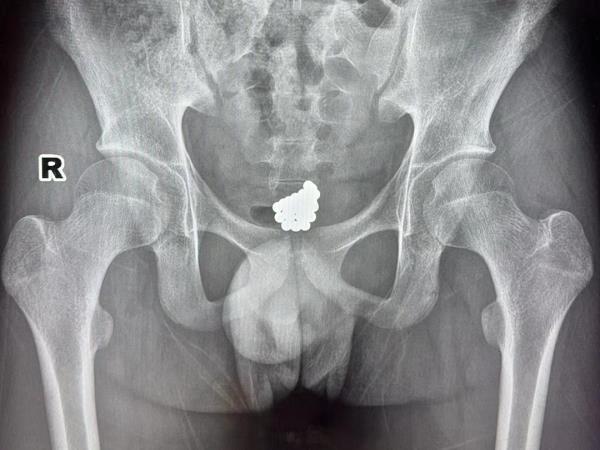

经过初步检查,小杰的尿道口呈现红肿的情况。随后,小杰又到放射科进行了详细检查。这一查,让在场的医生也不禁一愣,一坨小珠子堆积在小杰的盆腔区域,看样子还不少啊。

小杰的影像检查图

由于小杰年纪尚小,情况比较特殊,经过严密细致的讨论后,医生决定为小杰进行微创手术,将珠子取出来。

手术一开始还不太顺利,医生本来打算用平常用于取泌尿结石的“套石篮”将珠子一颗一颗“套”出来,但多次尝试,那珠子就是“雷打不动”。思索了一番,医生将工具换成了电切镜。

电切镜自带摄影系统,可以扩张尿道,且前头有个电切环可以尝试将珠子取出。换了工具之后,操作是顺畅了许多,但由于珠子带有磁力,全部窝在一起“抱团取暖”,费了好一番功夫,医生才将第一颗珠子取出来。

“万事开头难”,开了头后面就顺畅多了。取出第一颗珠子之后,医生很快又顺利取出一串珠子,手术经历大概半小时,珠子全部被取出。术后,手术团队一数,珠子竟然有整整30颗。